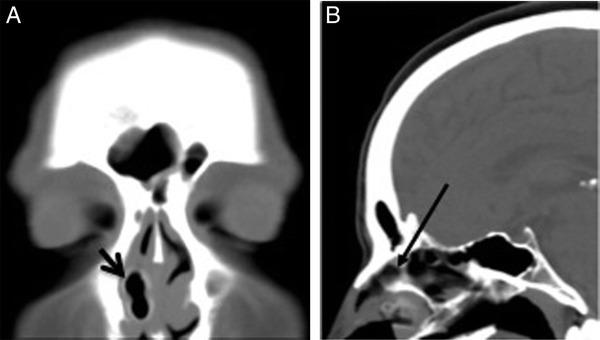

Internal nasal dilators are widely used but have not been reported to cause severe symptoms. We describe a case in which a male adult had accidentally, during sleep, inhaled a nasal dilator into his right nasal cavity, and we review the relevant literature. A PubMed search was performed of nasal dilators, especially of the internal types, including "Nasaline Snooze'" (ENTPro, Stockholm, Sweden). A foreign body in adults may be an inhaled nasal dilator. It may be overlooked on computed tomography scans, and thorough inspection of the nose is diagnostic.

鼻内扩张器被广泛使用,但尚未有导致严重症状的报道。我们描述了一例男性成年人在睡眠中意外将鼻内扩张器吸入右鼻腔的病例,并回顾了相关文献。我们在PubMed上搜索了鼻内扩张器,特别是包括“Nasaline Snooze”(瑞典斯德哥尔摩ENTPro公司)在内的内置型鼻内扩张器。成年人鼻腔内的异物可能是吸入的鼻内扩张器。在计算机断层扫描中可能会被忽视,而对鼻腔进行彻底检查可做出诊断。